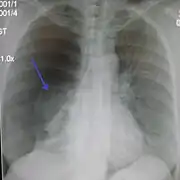

Chest X-ray

A plain chest radiograph, ideally with the X-ray beams being projected from the back (posteroanterior, or "PA"), and during maximal inspiration (holding one's breath), is the most appropriate first investigation.[30] It is not believed that routinely taking images during expiration would confer any benefit.[31] Still, they may be useful in the detection of a pneumothorax when clinical suspicion is high but yet an inspiratory radiograph appears normal.[32] Also, if the PA X-ray does not show a pneumothorax but there is a strong suspicion of one, lateral X-rays (with beams projecting from the side) may be performed, but this is not routine practice.[15][19]

Anteroposterior inspired X-ray, showing subtle left-sided pneumothorax caused by port insertion

Anteroposterior inspired X-ray, showing subtle left-sided pneumothorax caused by port insertion Lateral inspired X-ray at the same time, more clearly showing the pneumothorax posteriorly in this case

Lateral inspired X-ray at the same time, more clearly showing the pneumothorax posteriorly in this case Anteroposterior expired X-ray at the same time, more clearly showing the pneumothorax in this case

Anteroposterior expired X-ray at the same time, more clearly showing the pneumothorax in this case Chest X-ray showing a pneumothorax on the right (left in the image), where the absence of lung markings indicates that there is free air inside the chest

Chest X-ray showing a pneumothorax on the right (left in the image), where the absence of lung markings indicates that there is free air inside the chest Chest X-ray showing the features of pneumothorax on the left side of the person (right in image)

Chest X-ray showing the features of pneumothorax on the left side of the person (right in image)

It is not unusual for the mediastinum (the structure between the lungs that contains the heart, great blood vessels, and large airways) to be shifted away from the affected lung due to the pressure differences. This is not equivalent to a tension pneumothorax, which is determined mainly by the constellation of symptoms, hypoxia, and shock.[13]

The size of the pneumothorax (i.e. the volume of air in the pleural space) can be determined with a reasonable degree of accuracy by measuring the distance between the chest wall and the lung. This is relevant to treatment, as smaller pneumothoraces may be managed differently. An air rim of 2 cm means that the pneumothorax occupies about 50% of the hemithorax.[15] British professional guidelines have traditionally stated that the measurement should be performed at the level of the hilum (where blood vessels and airways enter the lung) with 2 cm as the cutoff,[15] while American guidelines state that the measurement should be done at the apex (top) of the lung with 3 cm differentiating between a "small" and a "large" pneumothorax.[33] The latter method may overestimate the size of a pneumothorax if it is located mainly at the apex, which is a common occurrence.[15] The various methods correlate poorly but are the best easily available ways of estimating pneumothorax size.[15][19] CT scanning (see below) can provide a more accurate determination of the size of the pneumothorax, but its routine use in this setting is not recommended.[33]

Not all pneumothoraces are uniform; some only form a pocket of air in a particular place in the chest.[15] Small amounts of fluid may be noted on the chest X-ray (hydropneumothorax); this may be blood (hemopneumothorax).[13] In some cases, the only significant abnormality may be the "deep sulcus sign", in which the normally small space between the chest wall and the diaphragm appears enlarged due to the abnormal presence of fluid.[16]